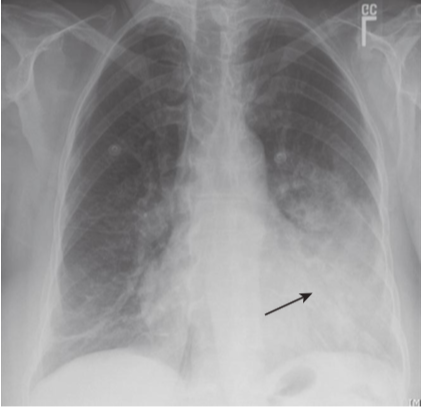

Loculated pleural effusions.

There are bilateral fluid collections (white and black arrows) that have unusual shapes and seem to defy gravity, because they are trapped in the pleural space, usually by adhesions. Loculated effusions can be suspected when an effusion has something other than a meniscoid shape or collects in a location other than the base of the lung (e.g., if the effusion were to remain at the apex of the hemithorax even if the patient were upright).